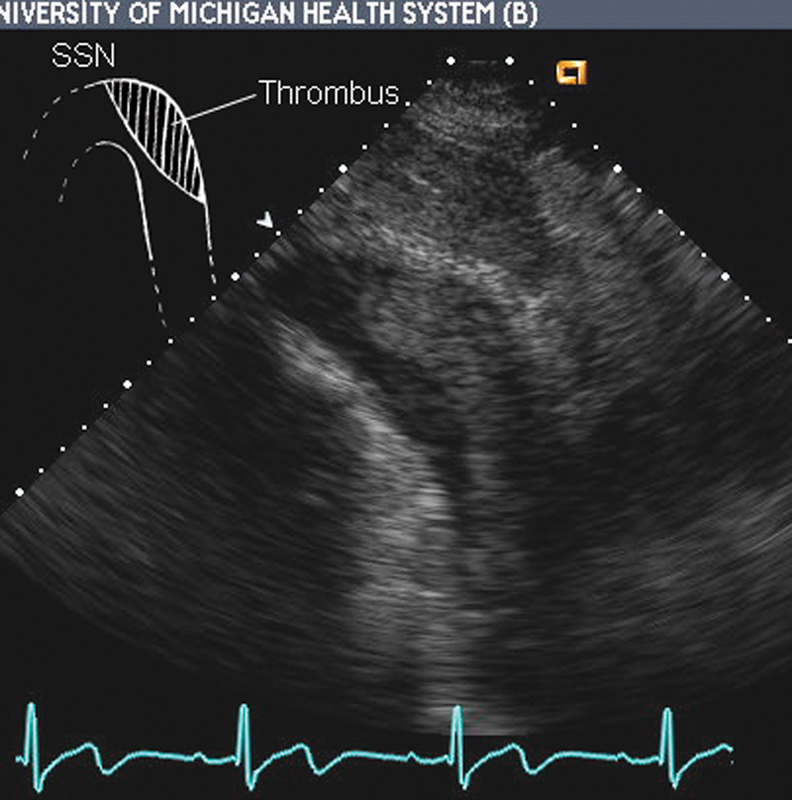

فحوصات تشخيصية لبعض امراض القلب والشرايين التاجية